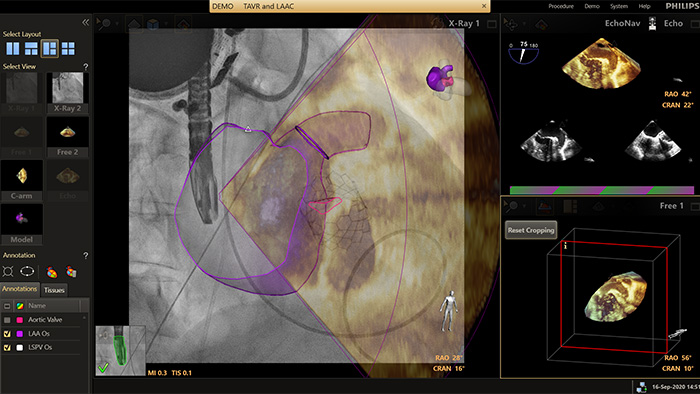

EchoNavigator reorients and combines ultrasound and X-ray information into a single augmented visualisation for guidance and device-tissue relationship assessment. In LAA occlusion EchoNavigator enables the following to elevate confidence and boost efficiency:

The HeartNavigator is a CT planning and live overlay guidance solution using automatic heart model segmentation of anatomy to improve ease of use, speed and reproducibility. In LAA occlusion, HeartNavigator enables: